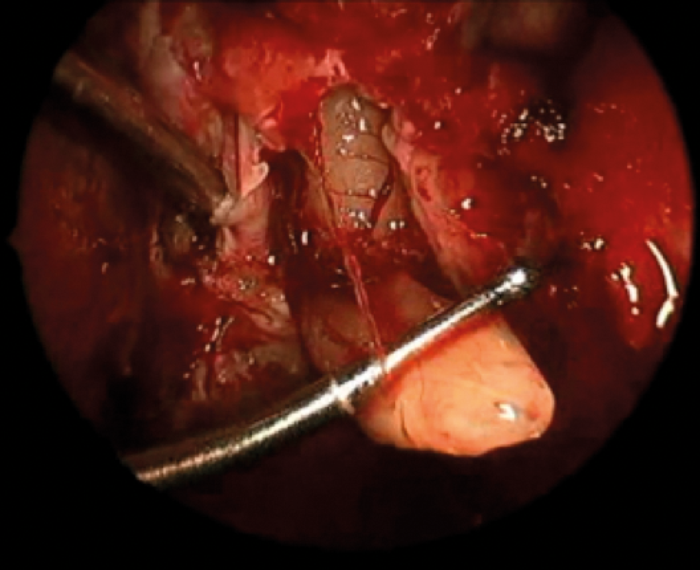

Surgical challenges in advanced or recurrent thyroid malignancy

The management of thyroid malignancy and extent of surgery is controversial, especially considering the limitations of preoperative diagnosis. Neil Tolley provides guidance and reminds us of our responsibility not to over-treat. In the UK, 16% of thyroidectomies are performed for...